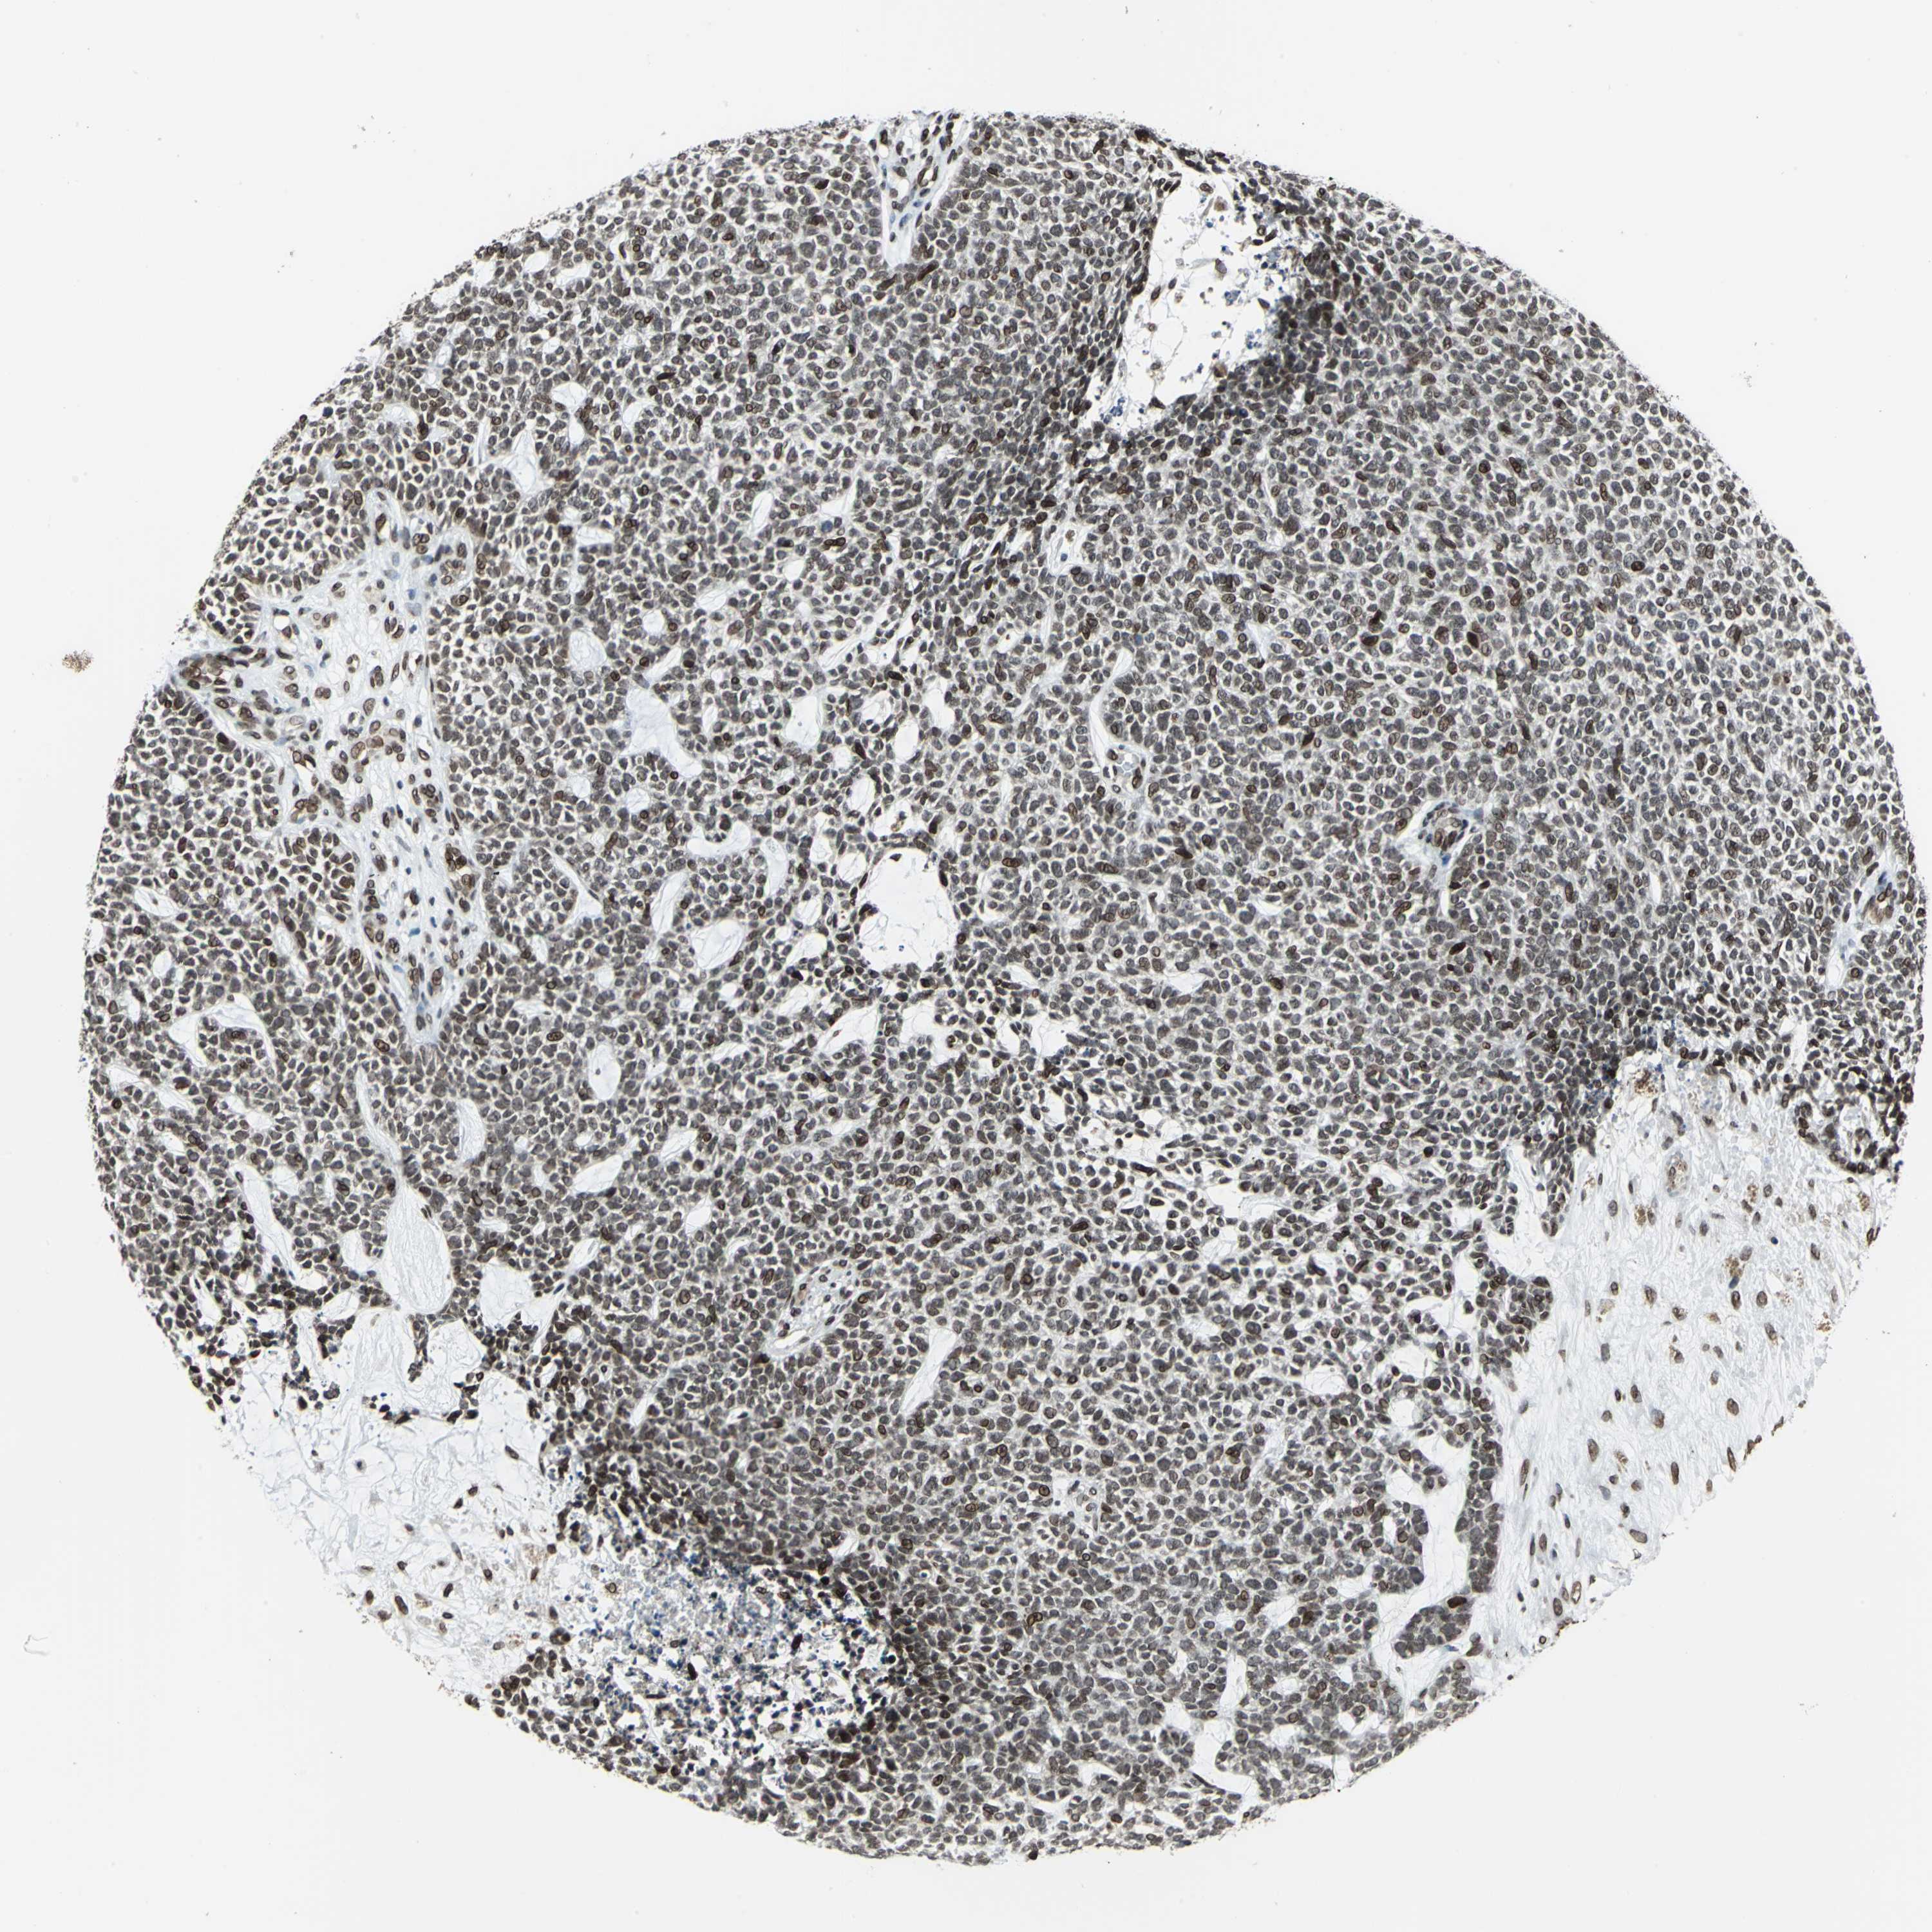

CANCER SKIN CANCER Show tissue menu

SKIN CANCER - Protein expressioni

A mouse-over function shows sample information and annotation data. Click on an image to view it in a full screen mode. Samples can be filtered based on level of antibody staining by selecting one or several of the following categories: high, medium, low and not detected. The assay and annotation is described here.

Antibody stainingi

Antibody staining in the annotated cell types in the current human tissue is reported as not detected, low, medium, or high, based on conventional immunohistochemistry profiling in selected tissues. This score is based on the combination of the staining intensity and fraction of stained cells.

Each image is clickable and will lead to virtual microscopy that enables deeper exploration of all samples and also displays staining intensity scores, fraction scores and subcellular localization as well as patient and tissue information for each sample.

Antibody HPA006312

Antibody HPA016995

Squamous cell carcinoma, NOS

Basal cell carcinoma

Squamous cell carcinoma in situ, NOS

Squamous cell carcinoma, metastatic, NOS

Adnexal tumor, benign